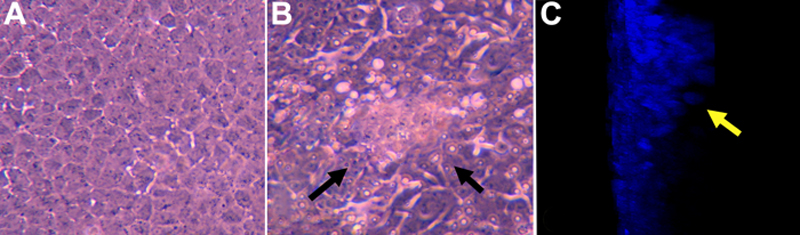

Figure 1. Cultured rat lens epithelial explants

The phase contrast photographs represents a control (A) and a TGF-β2/FGF-2 treated lens epithelial explant (B). C shows a confocal z-stack section (a y-axis projection) of a TGF-β2/FGF-2 treated lens epithelial explant. The control rat explant demonstrates a regular monolayer of lens epithelial cells while the TGF-β2/FGF-2 treated explants (B and C) formed mutilayer plaques (arrows). D: The video (below) demonstrates a confocal z-stack on a y-axis projection of a control explant stained for α-SMA (green) and nuclei (DAPI:blue). This video shows a single layer of cells with no staining α-SMA.